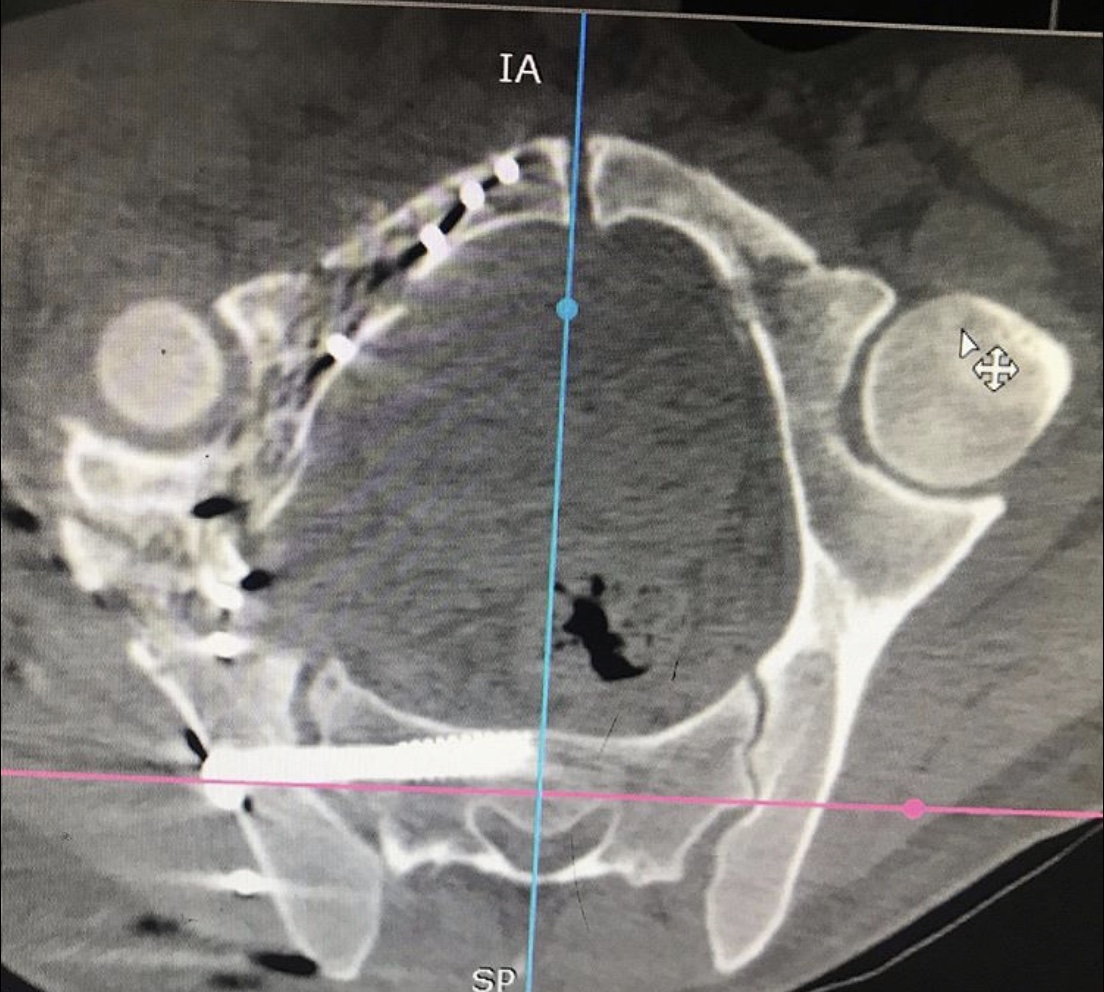

Перелом таза – тяжелейшая травма костей скелета, уступающая по опасности только травмам позвоночника и черепа. Она отличается особой опасностью, так как ее сопровождают обильная потеря крови и шока. Пострадавшему требуется экстренная врачебная помощь, иначе высок риск гибели. Даже при срочном врачебном вмешательстве не всегда удается спасти пострадавшего, который может погибнуть от кровопотери или осложнений болевого травматического шока.

Но к врачам-травматологам Городской клинической больницы № 7 Казани этот пациент поступил лишь спустя месяц после травмы. Врач – травматолог клиники Руслан Закиров признается: «Они в другом городе лечились. Жизнь спасали. К сожалению, не во всех больницах есть возможности для хирургии таза».

Пациента, что называется, «собрали».

Была выполнена открытая репозиция, остеосинтез пластинами.